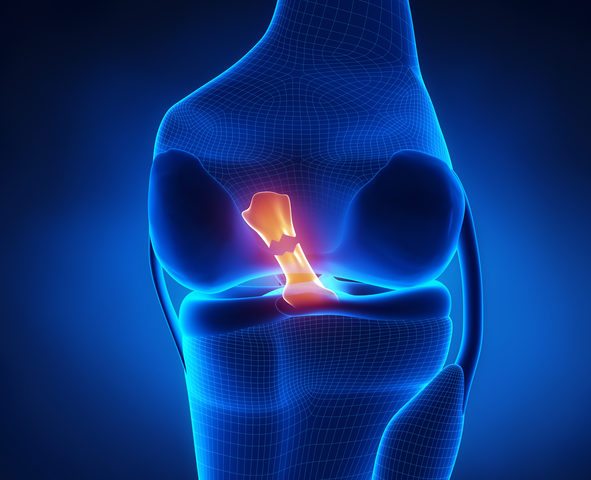

What is An ACL Tear, and How is It Treated?

If you ever had any sort of injury, especially a knee injury, you probably appreciate how your knees power you through various sports and activities: kicking, jumping, running, and pivoting. To avoid knee injuries, it helps to understand how your knees work and what you can do to protect or support them. What’s in a Knee?…